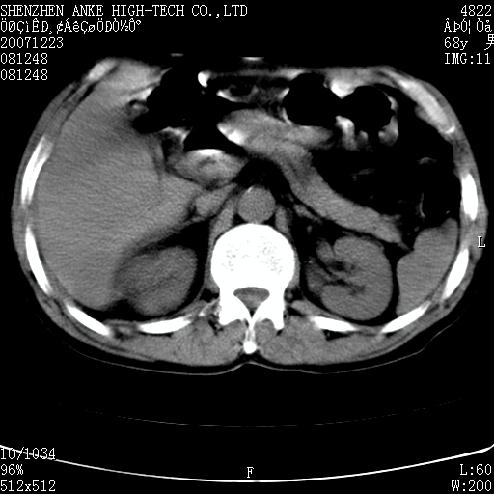

患者:男,63岁,2年前胆囊切除术后,现右上腹部剧烈疼痛近2天.

有无外伤史?右肾包膜下血肿可疑。

主要是问右肾有没有问题?患者无明显外伤史.

未见异常,病人差闭气,伪影较多.

肠道准备不好,干扰影大。

肠道气体伪影干扰太大了,应该是干扰所致,未见明显异常。

肠道准备不好,胃底后壁显示不清,右肾改变考虑为伪影。

上腹部ct平扫未见明显异常。(肠道气体较多,患者呼吸了)